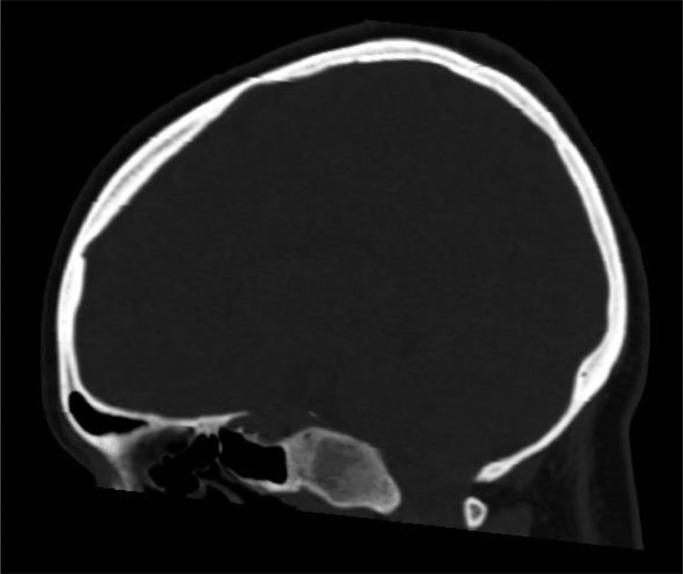

Fibrous dysplasia is a benign, congenital skeletal disorder which leads to the formation of fibro-osseous intramedullary bone lesions. Clival fibrous dysplasia is a rare variant which commonly presents asymptomatically with no findings on examination and is often picked up incidentally on radiological investigation. A 39-year-old female presented with a sudden onset headache of 3 days' duration alongside diplopia and right lower limb weakness upon examination. Computerized tomography head scan revealed an expansile clivus with a ground-glass appearance, magnetic resonance imaging brain scan revealed a predominantly hypointense signal on T1- and T2-weighted images and subsequent whole-body bone imaging confirmed the diagnosis of monostotic clival fibrous dysplasia. This case highlights the importance of considering monostotic clival fibrous dysplasia as a differential diagnosis in patients presenting with sudden onset symptoms of headache alongside cranial and peripheral nerve involvement, when other more sinister causes have been excluded.

骨纤维异常增殖症是一种良性先天性骨骼疾病,可导致骨髓内纤维性骨病变的形成。斜坡骨纤维异常增殖症是一种罕见的变异类型,通常无症状,检查无异常发现,常在影像学检查时偶然发现。一名39岁女性因突发头痛3天就诊,检查时伴有复视和右下肢无力。头颅计算机断层扫描显示斜坡膨胀,呈磨玻璃样外观,脑部磁共振成像扫描显示在T1加权和T2加权图像上主要为低信号,随后的全身骨成像确诊为单发性斜坡骨纤维异常增殖症。该病例强调,当排除其他更严重病因时,对于出现突发头痛症状并伴有颅神经和周围神经受累的患者,应考虑单发性斜坡骨纤维异常增殖症作为鉴别诊断。